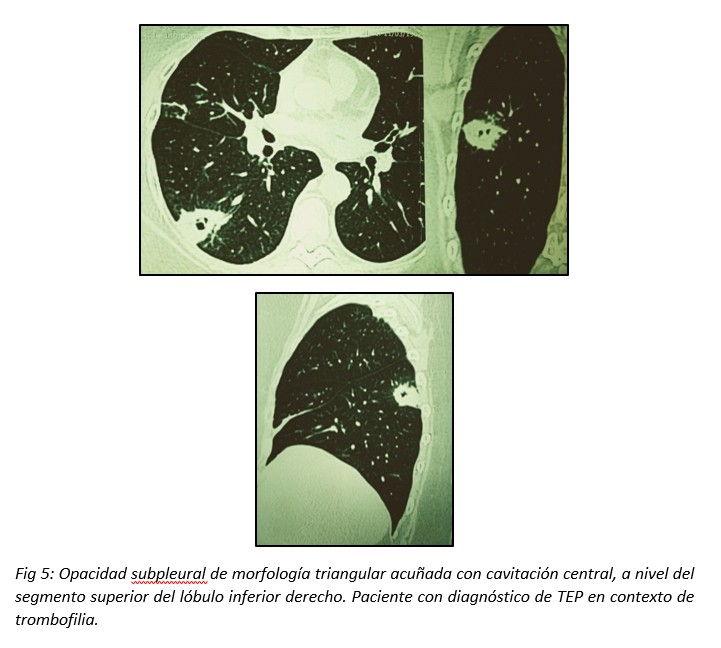

La cavitación es rara, y suele asociarse al embolismo séptico. En el contexto de un TEP la frecuencia de cavitación es del 4-5%.14,15 Puede representar una cavitación pulmonar aséptica o una sobreinfección de la región afectada. Los IP cavitados podrían predominar en lóbulos superiores, siendo habitualmente únicos con área de consolidación adyacente.16 (Fig 5)